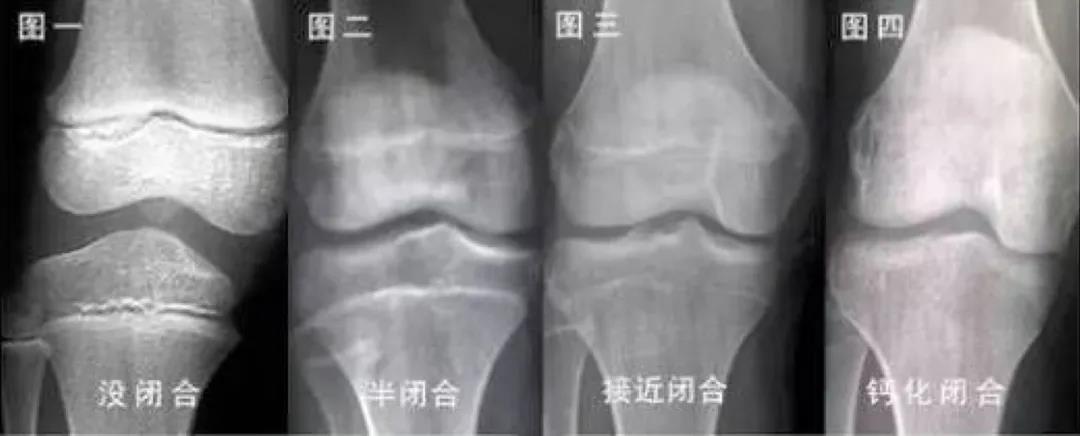

生长板存在固有的程序性变化,随着时间的推移,生长板出现功能性和组织性的衰老变化,软骨细胞不再具有增殖、骨化的能力,此时生长板就会闭合,也就是我们经常听到的“骨骺线闭合”,身高便不再增长。

在人体骨骼发育过程中,骨化中心出现的时间、骨化速度和骨骺与干骺端形态的变化,它们的闭合时间都呈现一定的规律性、连续性和阶段性,不同阶段的骨头具有不同的特点。

骨龄与生长板结构性变化存在密切的关系,骨龄小代表着生长空间足、还能长得更高,骨龄大说明生长空间小、身高增长的时间少。